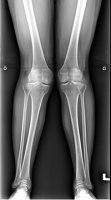

수 있다 내반슬과 외반슬의 차이점 이제 정확히 알겠죠? 내반슬은 다리가 바깥으로 휘어있으며 외반슬은 다리가 안쪽으로 휘어 있는 상태를 보이는 질환입니다. 내반슬, 외반슬의 경우 다리가 휘어진

! 그래서 오늘은 외반슬이라 불리는 일명 엑스다리.. 를 위한 스쿼트 운동을 실시했습니다. 정상적인 다리모양이 1번 , 안짱다리라 불리는 O다리 내반슬, 엑스다리 외반슬 형태입니다. 오른쪽